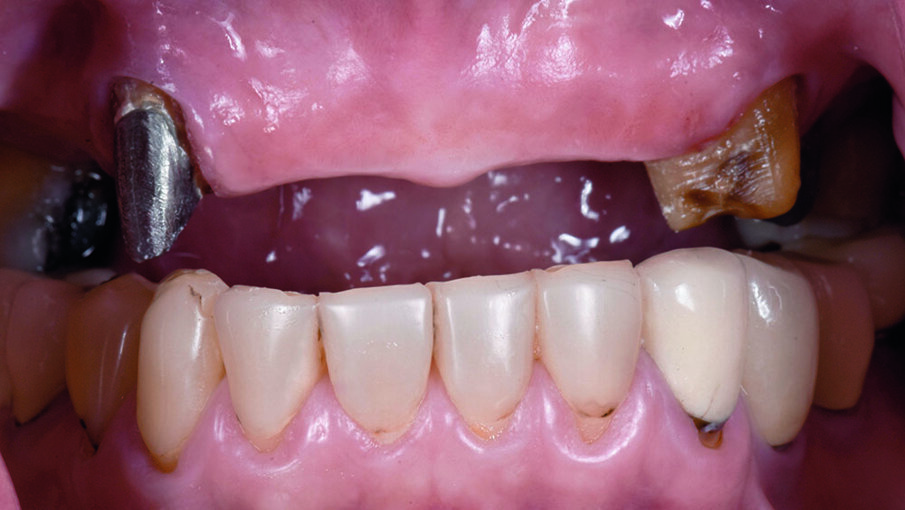

A 61-year-old Thai female presented with loosening 9-unit fixed dental prostheses (FDPs). Her chief complaint concerned her loose and unpleasing front teeth with unsatisfactory removable gingiva.

The initial clinical examination revealed a long-span Porcelain-Fused-to-Metal (PFM) FDPs of teeth 14-25 fixed with temporary cement since 2009 at private hospital (Fig 1,2). The patient had maxillary hard and soft tissue defects associated with alveolar ridge resorption and loss of lip support. Removable Acrylic Gingival Veneer (AGV, Fig 3.) was used to cover those FDPs in order to improve extra-oral soft tissue profile (Fig 4.). Without AGV, the patient has concave profile (Fig 5.). FDPs were removed to evaluate the existing abutments condition (Fig 6.). Abutment teeth 13,24,25 had first degree mobility. Panoramic XRAY (Fig 7.) revealed that tooth 13 had cast post and core with vertical root fracture. Tooth 25 was endodontically treated with a periapical lesion. After thorough diagnosis and analysis, the treatment plan was presented to the patient with the following phased treatment approach:

Fig 1. Pre-operative Fixed Dental Prosthesis with Acrylic Gingival Veneer

Fig 2. Pre-operative without AGV

Fig 6. Pre-operative without 9-unit FDPs